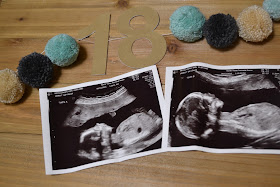

Anatomy Scan

Today we went in for our second Level II Ultrasound with the perinatologist. Because our twin pregnancy is considered high risk, I will have several over the course of my pregnancy. Which I am ok with, because it means we get to check in on our babies :)

Today was our official anatomy scan. So they took some extra time to measure our babies' organs, growth, weight, and to make sure they had all their important appendages. It took a little bit longer because they were SUPER active and wouldn't stay still. The poor sonographer seemed to get a little frustrated because every time she would get close to getting a measurement, they would move. But we finally got all the info we needed, and it was such a relief to hear that our babies are measuring right on track and that all looks well! Strong heartbeats, all organs and appendages look good, and they are looking healthy. That's all this mama needs to hear :)

Mike snuck a photo while we were trying to identify which baby was which :)

Baby A {Baby Boy}:

- Weighing 10 ounces

Baby B {Baby Girl}:

- Weighing 9 ounces